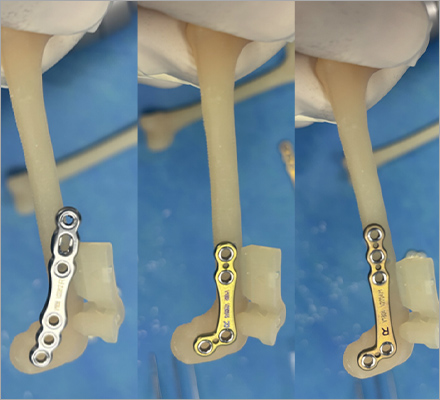

다양한 회사의 플레이트 제품을 가지고 있어서 환자 맞춤으로 수술이 가능합니다.

일반적으로 TPLO 수술 시 6홀 플레이트를 사용하는데

이 환자의 경우 뼈가 작아 5홀 플레이트를 사용하여 교정하였습니다.

슬개골탈구 3기 + 십자인대질환

- modified TPLO with jeil TPLO 1.5 modified plate(6 holes)

- 4.3kg, 치와와

특수하게 휘어진 Jeil medical 1.5 modified TPLO plate를 사용하여

소형견 환자도 안정적으로 슬개골탈구와 십자인대를 동시에 교정할 수 있습니다.

슬개골탈구 3기 + 십자인대질환

- modified TPLO with jeil TPLO 1.5 modified plate (6 holes)

- 4살 3.5kg, 말티푸

슬개골탈구 3기와 십자인대질환에 대해 modified TPLO 진행하였습니다.

Modified TPLO 전용 특수하게 휘어진 플레이트를 사용하였습니다.

다양한 크기/다양한 뼈 모양에 가능한 기구 보유하여 리허설을 통해서 환자에게 가장 적합한 플레이트 이용합니다.

Synthes plate vs fixin plate

fixin plate vs jeil medial plate

- 다양한 정형외과 회사 제품 보유로 환자 맞춤 수술 가능

- 다양한 크기/다양한 뼈 모양에 가능한 기구 보유

- 리허설을 통해서 환자에게 가장 적합한 플레이트 이용

보유 회사 제품: Fixin, Jeil Medical, Vi, Synthes